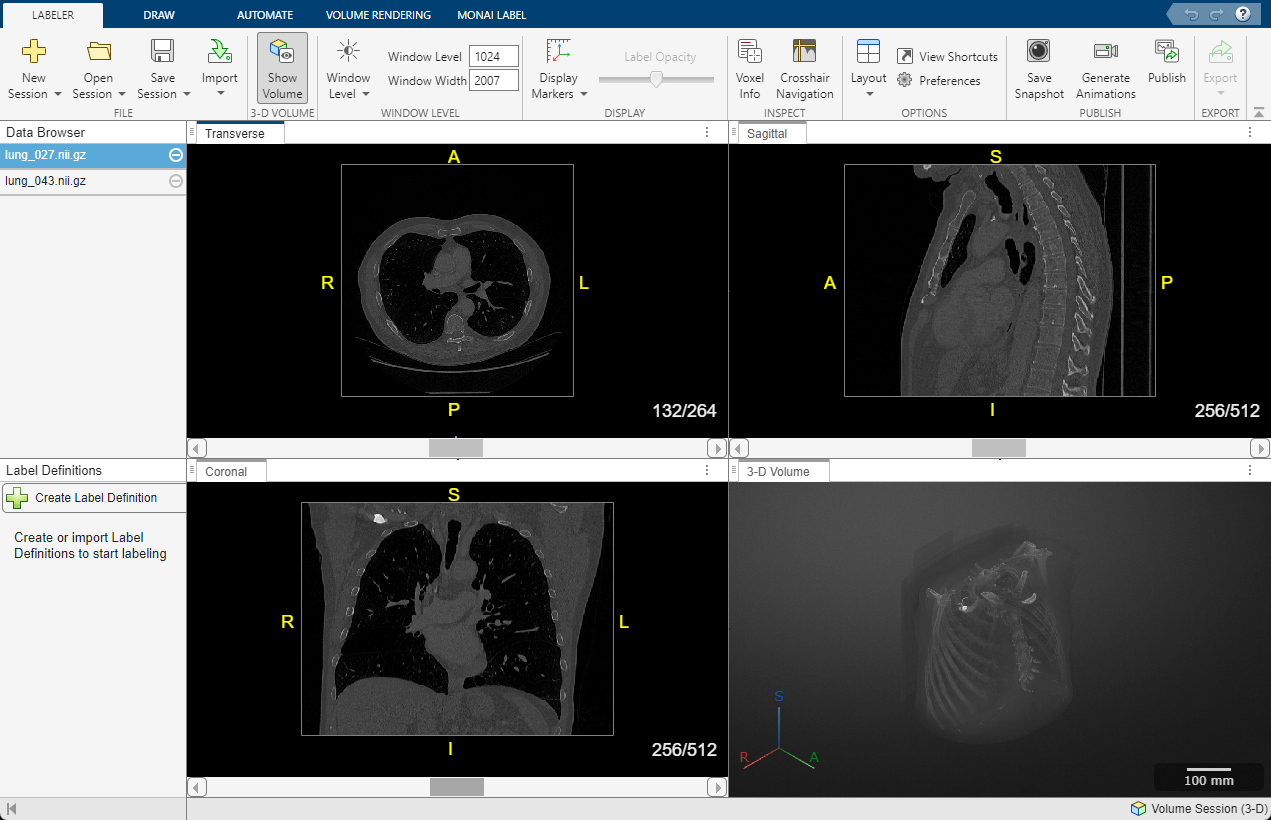

Imágenes DICOM transversales, sagitales, coronales y de volumen en 3D de una TC torácica con etiquetas.

TC torácica en 3D en formato DICOM visualizada con Medical Image Labeler en Medical Imaging Toolbox. (Consulte la documentación).